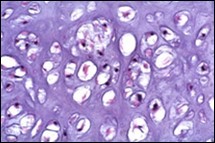

Figure 4.Enchondroma depicting lobules of hyaline cartilage with vacuolated cells and eccentric nuclei 12.

Figure 5.Enchondroma enunciating lobules of uniform cartilaginous cells with regular, centric nuclei and absence of mitosis 13.

Figure 6.Enchondroma exemplifying lobules of hyaline cartilage composed of enlarged, vacuolated cells with uniform nuclei. Focal calcification is absent 14

Figure 7.Enchondroma enunciating lobular hyaline cartilage with constituent vacuolated chondrocytes an uniform nuclei 15.

Figure 8.Enchondroma delineating hyaline cartilaginous cells with vacuolated cytoplasm and uniform nuclei 16.